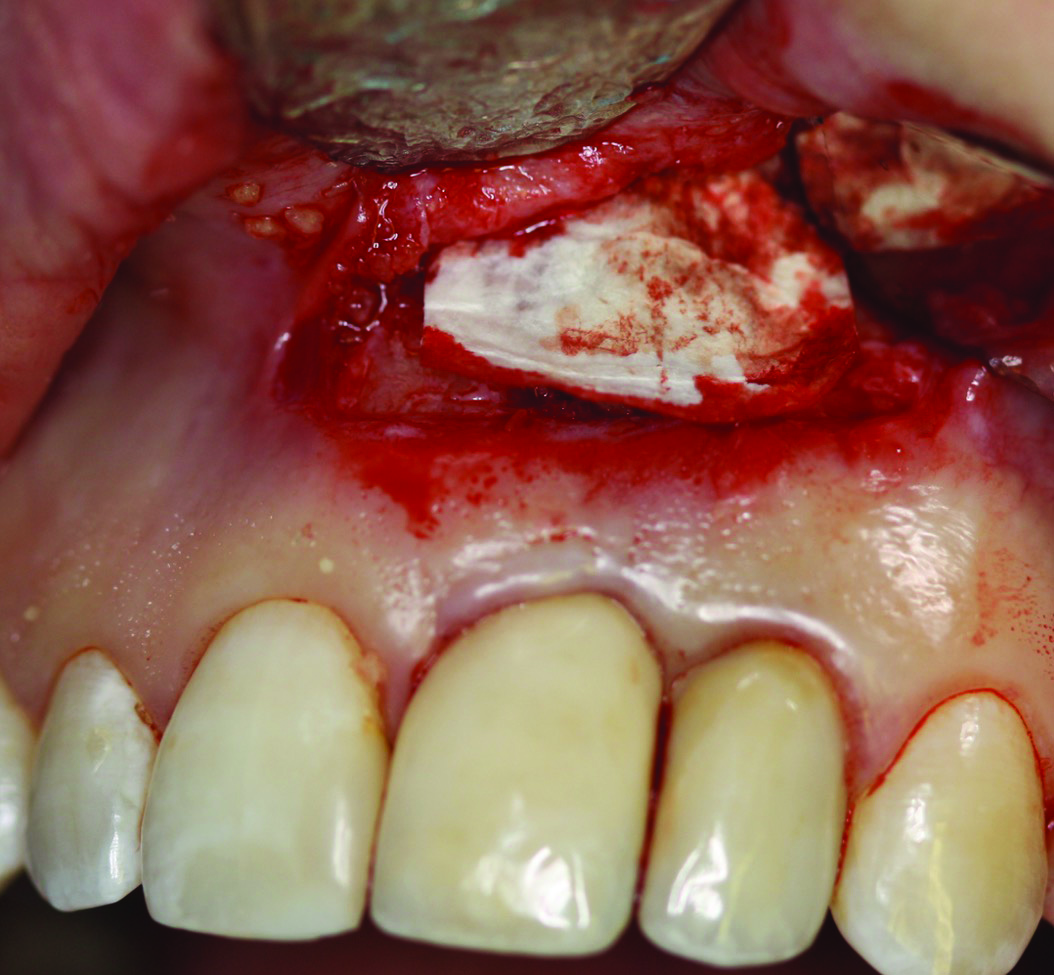

Fig 10. Case 2: FDBA bone allograft mixed with a small amount of doxycycline placed over the defect. The graft would be covered with a resorbable collagen membrane.

Figure 10